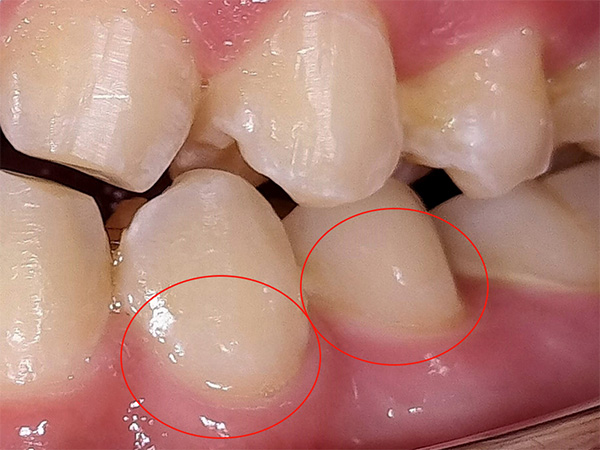

それはホワイトスポット(白濁)と呼ばれる歯の表面の変化で、初期虫歯やエナメル質の形成異常、矯正後の白斑などが原因で起こります。

白く見えている部分は、歯の内部に空洞ができ、光の反射が不均一になっている状態です。

ICONでは、その空洞に特殊な樹脂(レジン)を浸透させて埋めることで、歯の透明感を回復させ、白濁を目立たなくします。